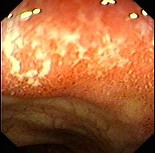

慢性腹泻患者,解黏液脓血便伴里急后重,多次粪便常规与培养均未发现致病菌及原虫。 肠镜检查如图,经柳氮磺胺吡啶治疗症状明显改善,本例诊断最应考虑()。

A:溃疡性结肠炎

B:Crohn病

C:结肠癌

D:肠结核

E:慢性细菌性痢疾